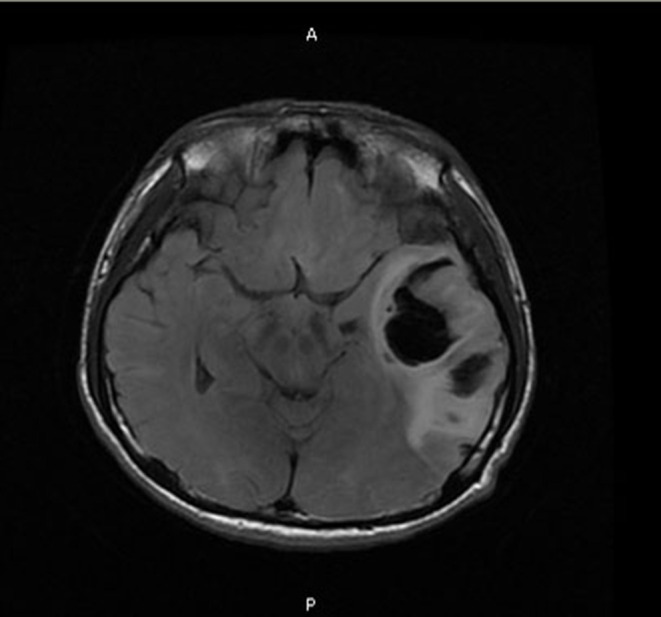

Methods and patient presentation: We report an 18-year-old student of EGPA complicated with intracerebral hemorrhage. The laboratory tests showed a continuous increase in eosinophils. The CT of head and chest showed cerebral hemorrhage and pulmonary infiltration.

Outcomes: At discharge, the patient's head and chest CT showed obvious absorption of intracranial hematoma and improvement of pulmonary infiltration. We reviewed 40 previously published cases of EGPA with intracerebral hemorrhage focusing on the clinical features and treatment of intracerebral hemorrhage caused by EGPA.